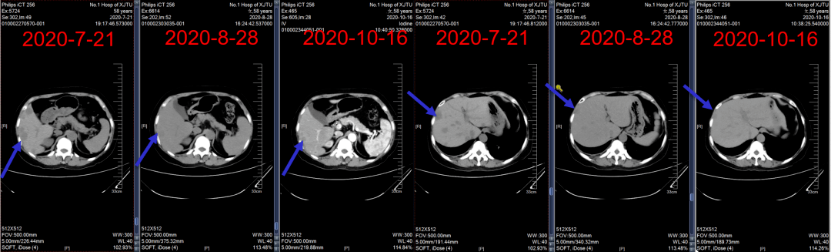

2020年7月23日~2020年10月16日,给予艾立布林(2 mg,d1,d8,q3w)×5周期抗乳腺癌治疗。

肺、肝脏转移病灶治疗2周期后部分缓解(PR),4周期后 SD。

图14:四线治疗期间随访肺部CT

图15:四线治疗期间随访肝脏CT